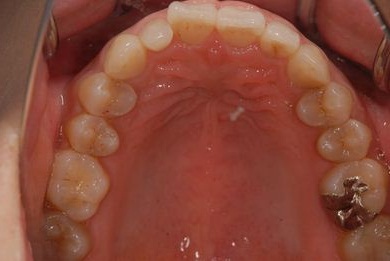

治療後

• 治療後